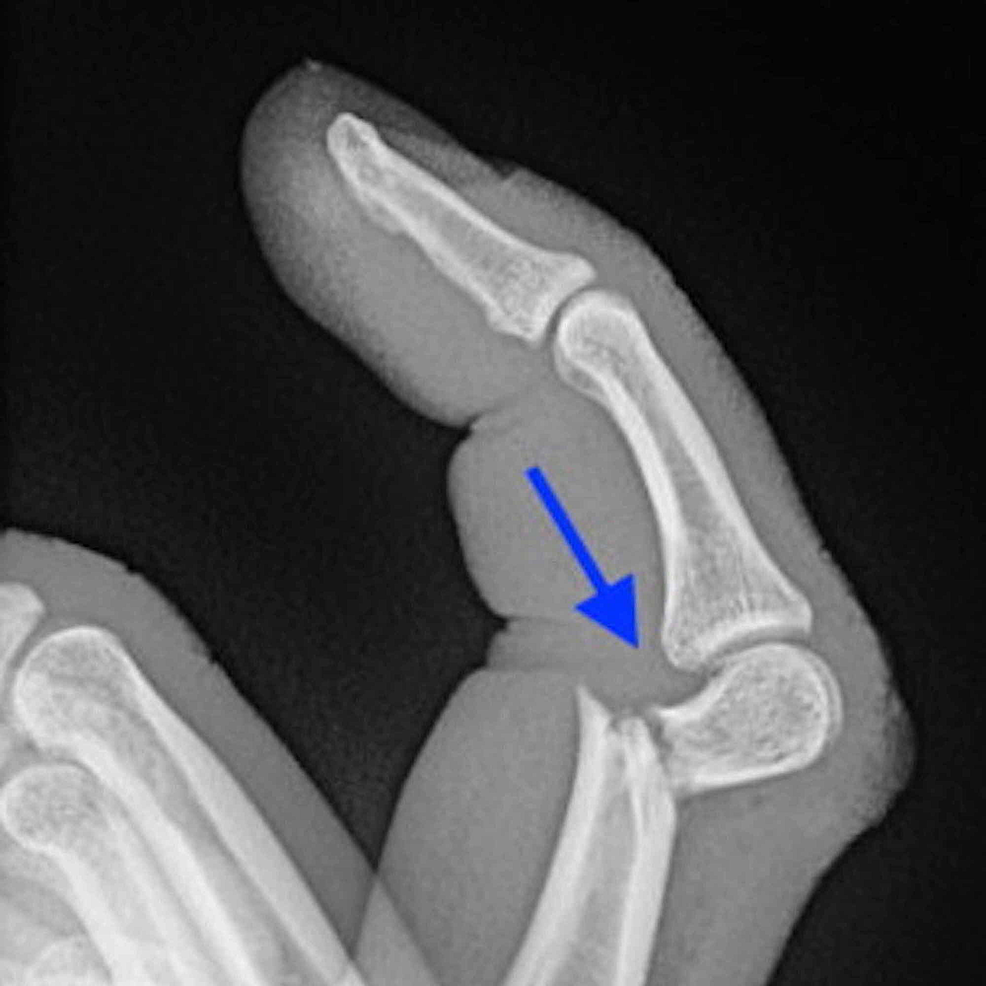

발가락 골절 증상·진단 포인트

- X-ray 2 방향 촬영이 1차 진단 표준

- 모호할 경우 CT/MRI 추가